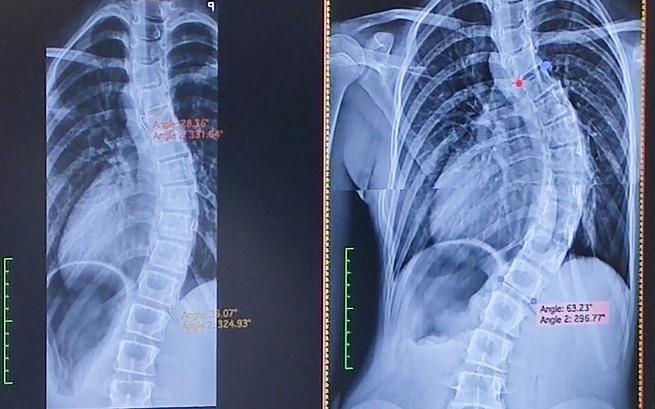

Skolioza ciągle postępuje. Niestety doszła do takiego momentu, że niezbędna jest operacja!

Możliwe, że będziemy musieli się jej podjąć poza granicami Polski. Przed nami wiele badań: krwi, płuc, echo serca.

Milenka, moja 11-letnia córka od urodzenia zmaga się z licznymi diagnozami. Nadmierna elastyczność stawów, gotyckie podniebienie, szewska klatka piersiowa, mocna skolioza...

To tylko niektóre z dolegliwości, które każdego dnia niszczą jej dzieciństwo. Lekarze podejrzewają, że córka cierpi na zespół Marfana, jednak aby to potwierdzić, potrzebne są niezwykle drogie badania genetyczne. Skolioza postępuje, zmusza córkę do chodzenia w gorsecie ortopedycznym. W styczniu najprawdopodobniej dostanie skierowanie na operację.